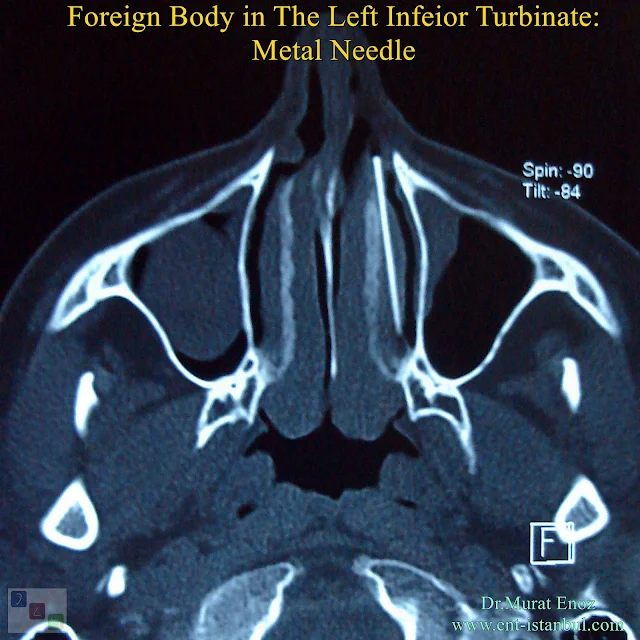

Above are the tomography sections of a patient who had undergone intranasal cauterization with needle-like metal objects inserted into the inferior turbinate. In the left lower nose, a foreign body that is compatible with a shining metal needle is seen. The needle is broken during the process and a large piece of needle is seen in the turbinate.

35 years old patients was adimitted my clinic with compliants of nasal blockage instead of previous several radiofrequency turbinate reduction procedures. On the paranasal sinus tomography, incidentally metal needle is seen in the left inferior turbinate. Endoscopic foreign body removal fom inferoior turbinate is planned. On the endoscopic there is no any abnormal finding except from turbinate hypertrophia.